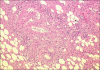

We report a case of Wunderlich's syndrome in an obese woman associated with massive retroperitoneal hemorrhage. Stable hemodynamic patient condition was obtained by selective arterial embolization. Since the first embolization of a renal angiomyolipoma in 1976 by Moorhead et al., highly selective renal arterial embolization of angiomyolipoma with rupture has become a procedure that offers greater efficacy, particularly in life-threatening cases.